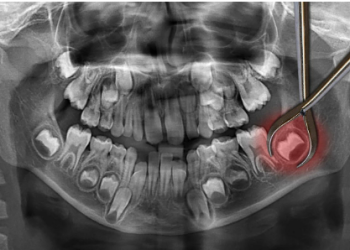

You may have heard about the ironically named wisdom teeth. Unfortunately, when you get your wisdom teeth, you are not...